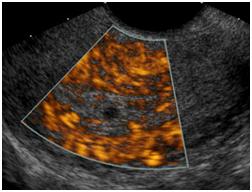

Ultrasound of the Pelvis1